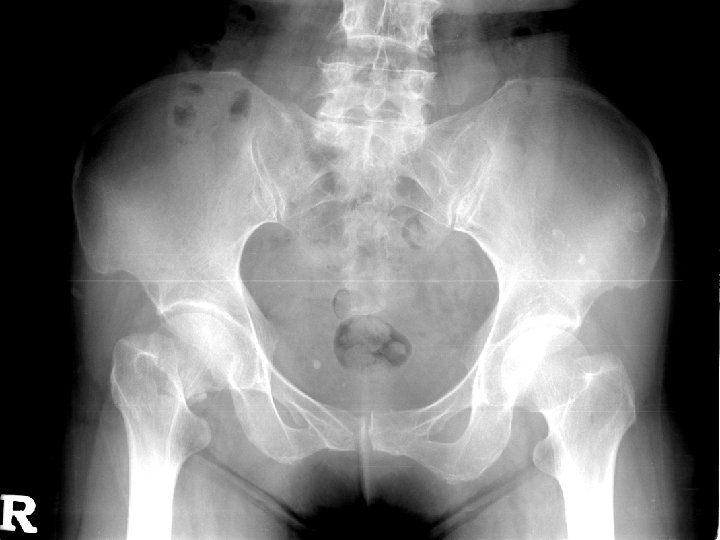

Patient profile n n Name:游 XX 菊 Gender: Female Age: 59 years old Chart number: 02766663

Chief complaint n Right hip painful deformity

Present illness n n The 59 year-old female was a victim of hypertension before. On 95. 3. 7, she suffered from slipped down and felt right hip pain and can’t walk. She was brought to our OPD for help. Severe pain with limited ROM was noted.

Physical examination n n Tenderness, swelling of the right hip ROM limitation (+), severe pain when moving

Tentative diagnosis n Right femoral neck fracture, Garden type III